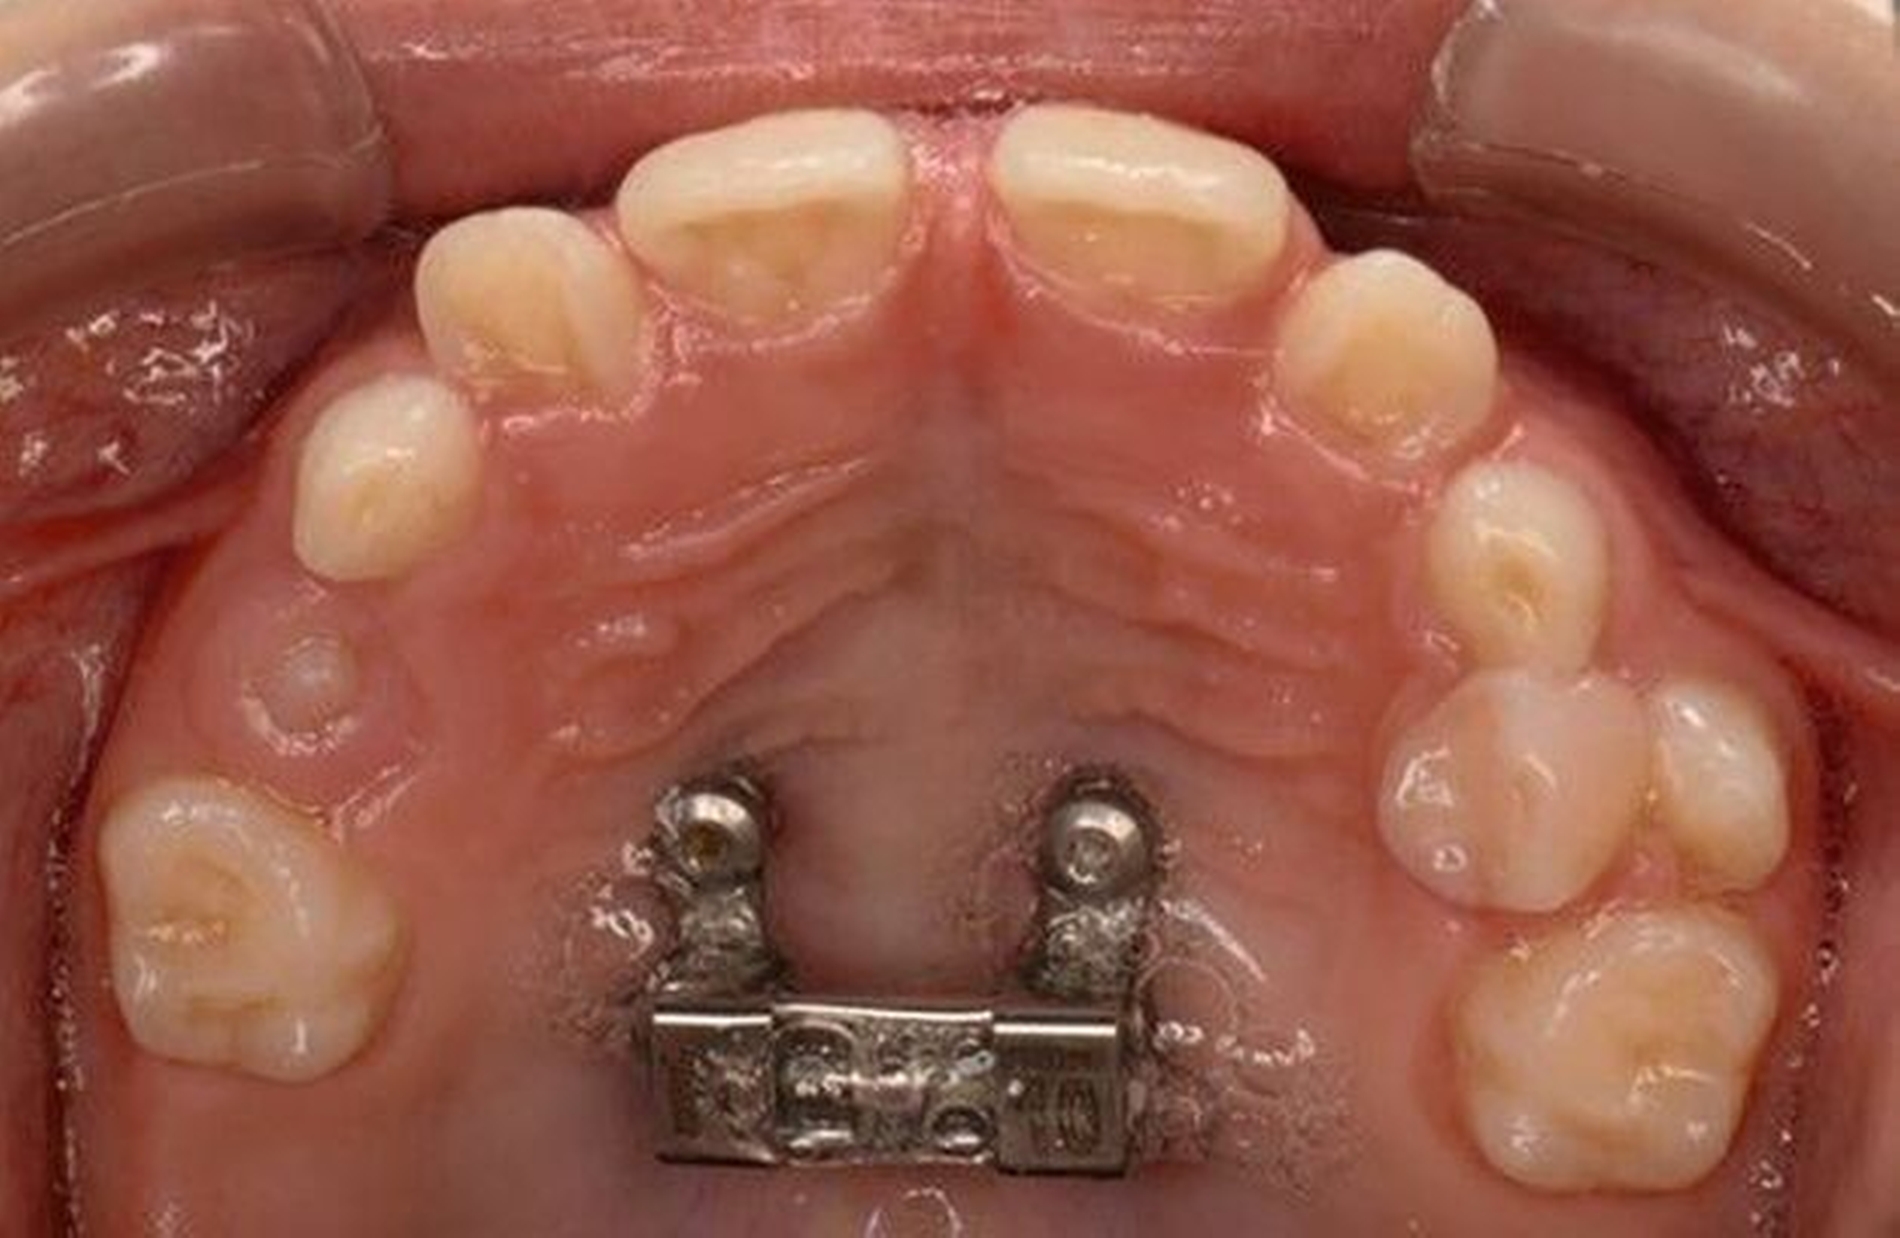

Die Eltern des Patienten wurden angewiesen, die Schraube einmal täglich zu aktivieren. Die gesamte Aktivierungszeit der Hyrax-Schraube betrug circa zehn Wochen. Während dieser Zeit vergrößerte sich die transversale Dimension des Oberkiefers um sieben Millimeter im posterioren Bereich (Milchmolaren) und um fünf Millimeter im anterioren Bereich (Milcheckzähne). Währenddessen trat ein mediales Diastema auf (Abbildungen 4b und 4c), das auf eine skelettale transversale Expansion des Oberkieferknochens hinwies. Nach der aktiven Expansionsphase der Hyrax-Apparatur wurde das Gerät für weitere Behandlungszwecke verwendet: Erstens als Retentionsgerät, um die bereits erzielte transversale Oberkieferbreite zu halten und zweitens als skelettal verankerte Apparatur zum Einstellen der retinierten und verlagerten Zähne mithilfe individuell angefertigter Kragarme. Hierfür wurde die Hyrax-Apparatur im zahntechnischen Labor modifiziert, indem Kreuzröhrchen für eine stationäre Befestigungen für die Drähte des Kragarms angebracht wurden.